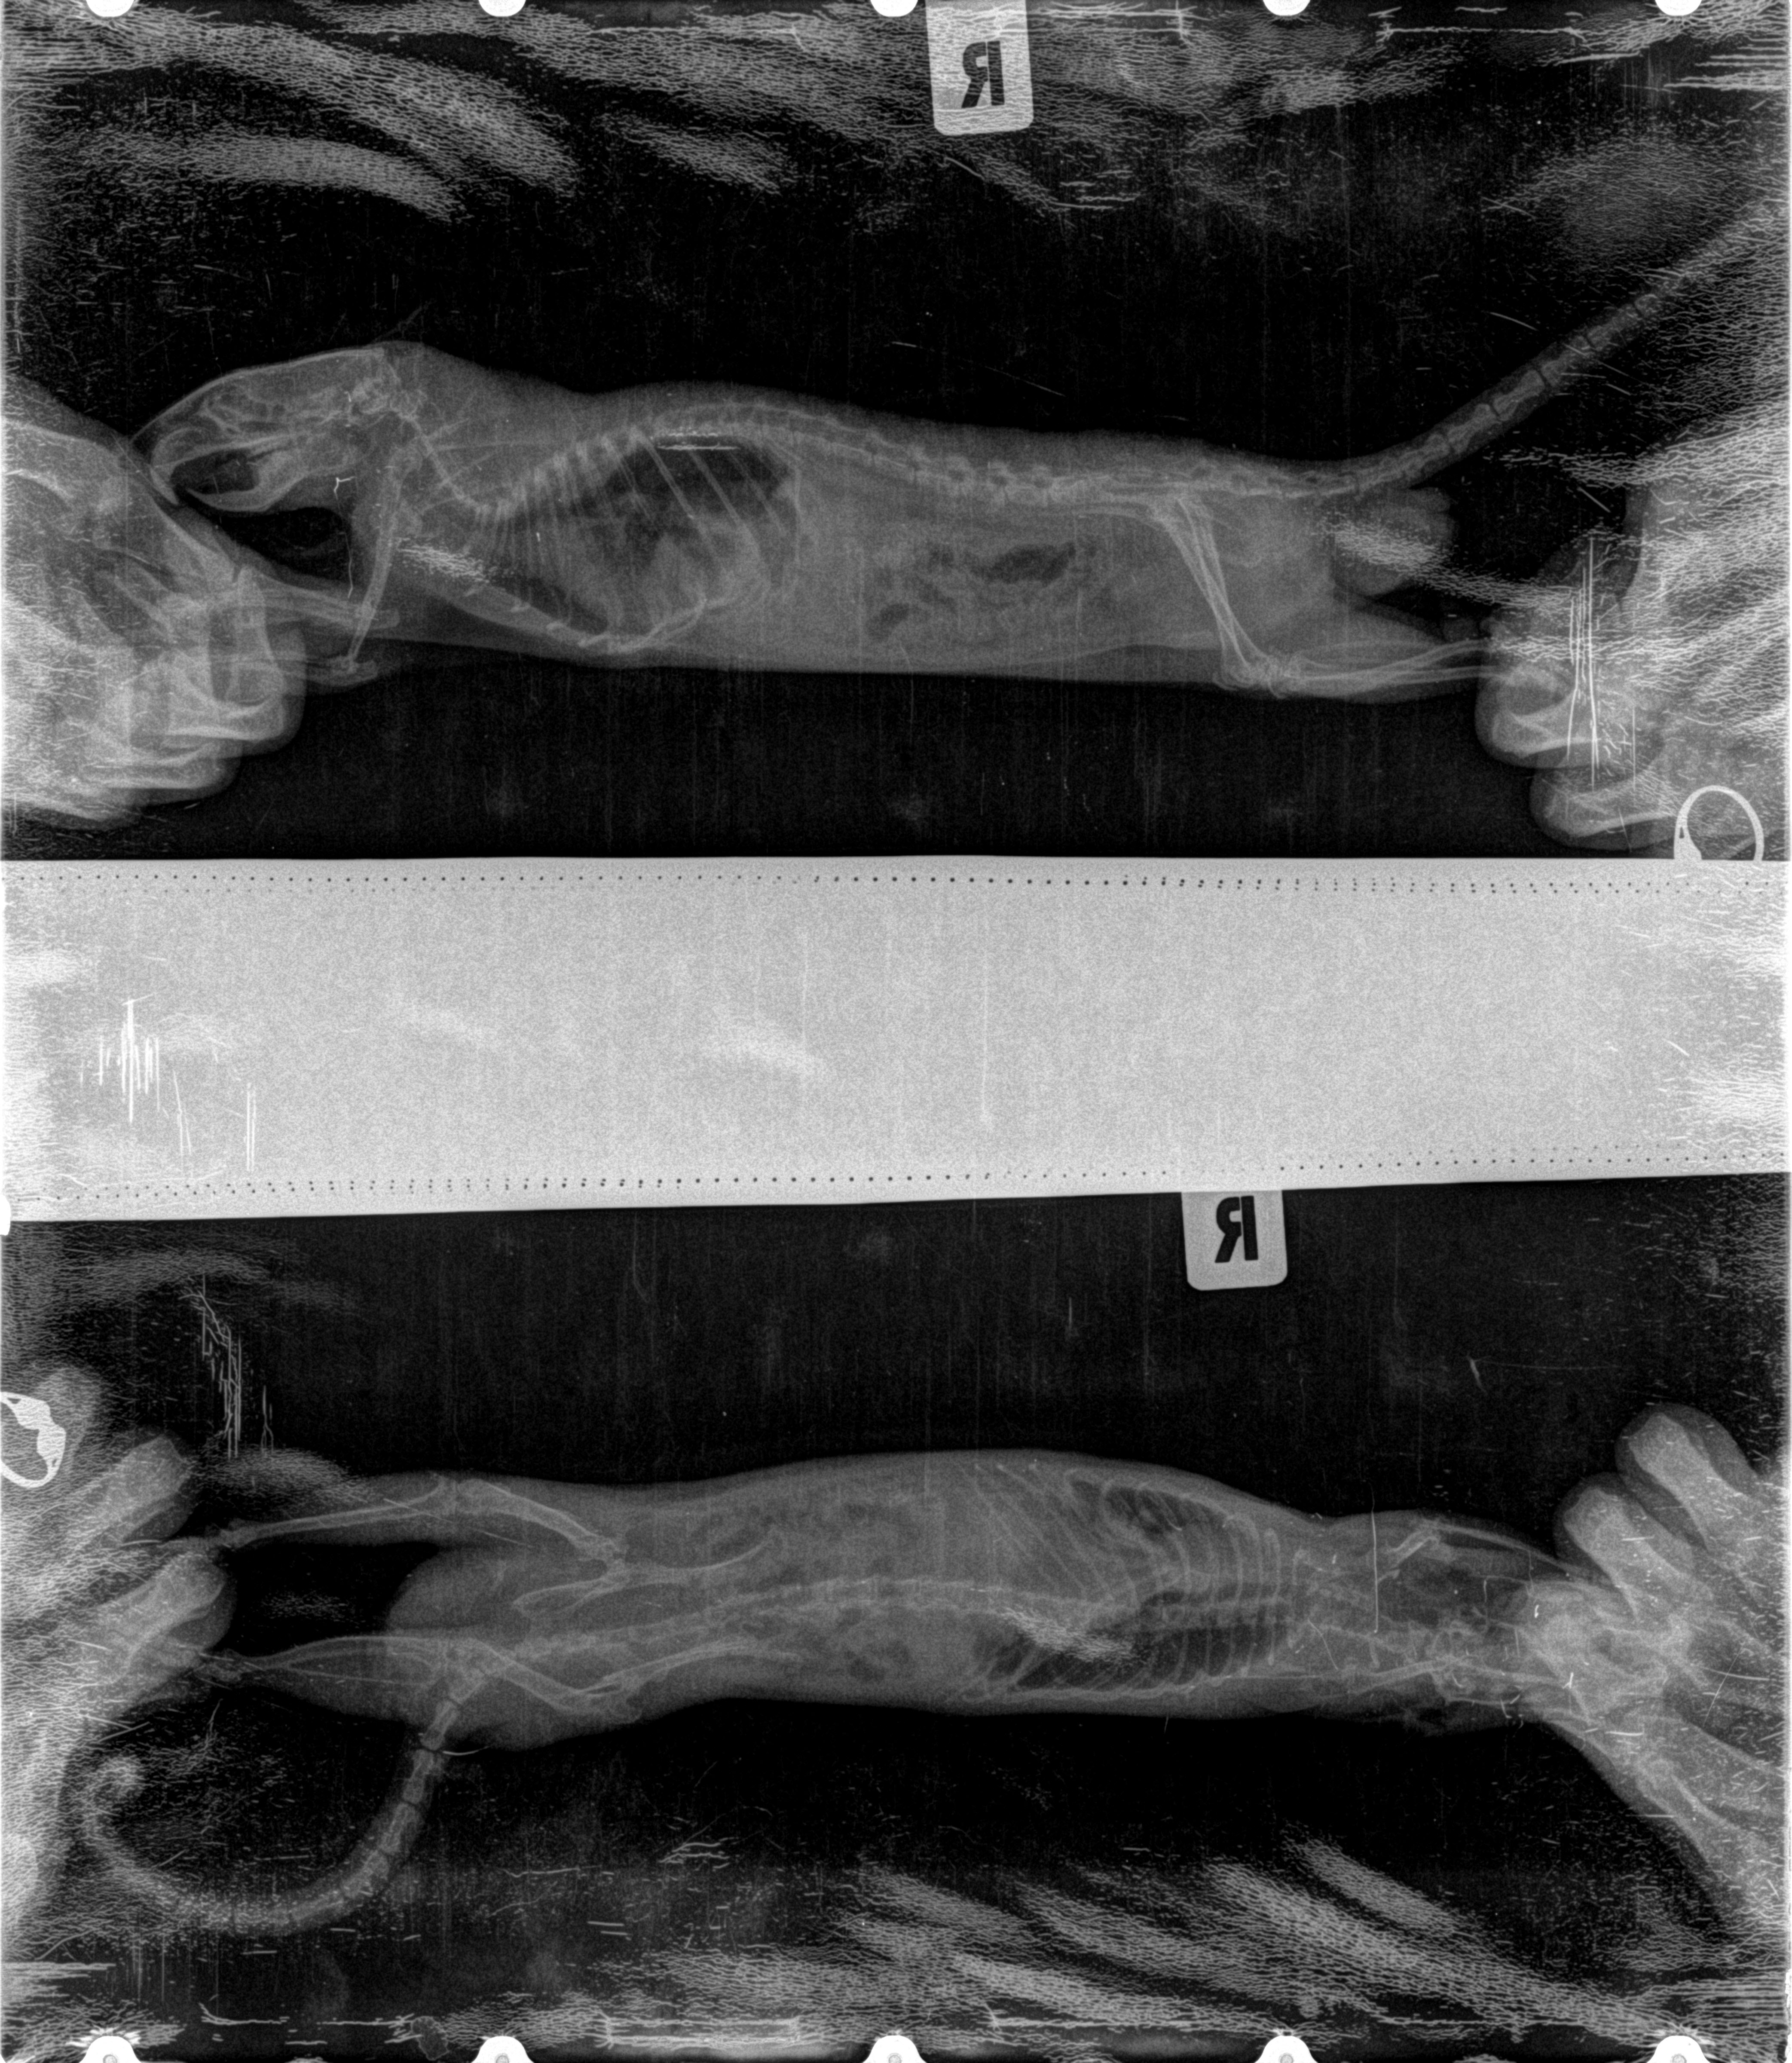

Доброго времени суток, помогите пожалуйста. У меня живет крыс-полупасюк, возраст 2,7 лет. Около 1,5 мес назад стал вялым, похудел, мало кушал, стал дышать боками, стал менее активным, небольшое количество порфирина вокруг носа. По рекомендации ветеринара прокололи байтрил 2,5% 5 дней 2 раза в день. Стало лучше, но продолжал дышать боками. Затем нашли схему лечения доксициклином, давали 10 дней 2 раза в день и 14 дней 1 раз в день. Крыс стал более активным, кушает, но не перестал дышать боками, медленнее бегает, чем до болезни. Около недели назад заметили, что крыс стал укать, похрюкивать, при физической активности (повертится минут 5 в руках) стал дышать ртом. Сделали рентген. Описание: на обзорной рентгенограмме легких в правой латеральной и вентродорсальной проекции визуализируется затемнения смешанного типа. На латеральной проекции не визуализируется тень диафрагмы. Рентген прилагаю,извините за качество, такое в ветеринарке сделали. Ратологов в городе не нашли, кому показать полечить крысика не знаю. Помогите пожалуйста, что делать, как лечить беднягу?

meneatrix, я не умею, к сожалению читать рентгеновские снимки и думаю, что Вам стоит еще зайти в раздел ветеринарии на Крысином Буме и посоветоваться там: http://rat.ru/forum/index.php?board=6.0

По Вашему описанию есть один симптом, который несколько настораживает - синеют лапки. Возможно там еще с сердцем есть проблемы серьезные. Надо чтобы разбирающиеся люди посмотрели снимок и проконсультировали. У нас на форуме нет, к сожалению, таких специалистов. Пожалуйста, создайте там темку - пусть посмотрят и подскажут. Дополнительные рекомендации могут быть совсем не лишними.